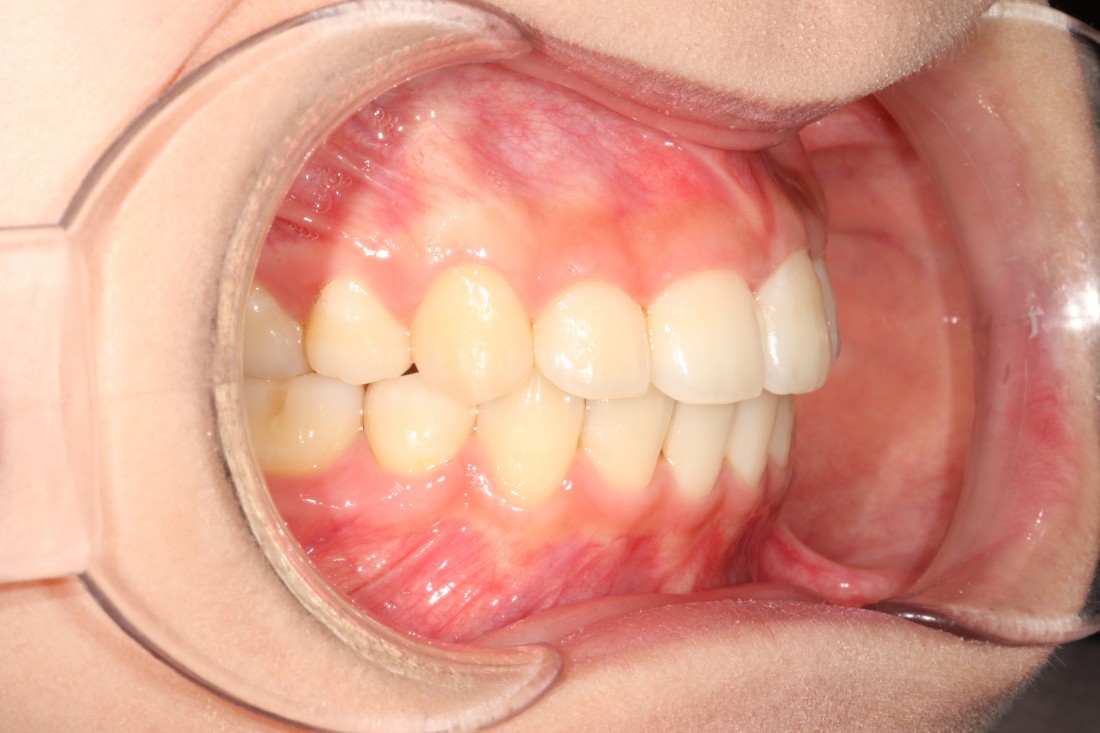

광주 성인 교정치과에서

충치치료와 교정진료를 동시에 받으신

성인 여성 환자분의 케이스입니다.

충치치료 전에는 은색 보철물이 있던 자리에

교정진료의 마무리와 동시에

치아색 보철물을 씌워서

치아교정 + 충치치료를 동시에 진행하였습니다.

광주 성인 치아교정의 경우

충치치료의 시기를 잘 판단하여

성공적인 진료를 완성할 수 있기 때문에

분과별 전문의가 협진하는

광주 성인 교정치과를 선택하시는 것이 좋습니다.